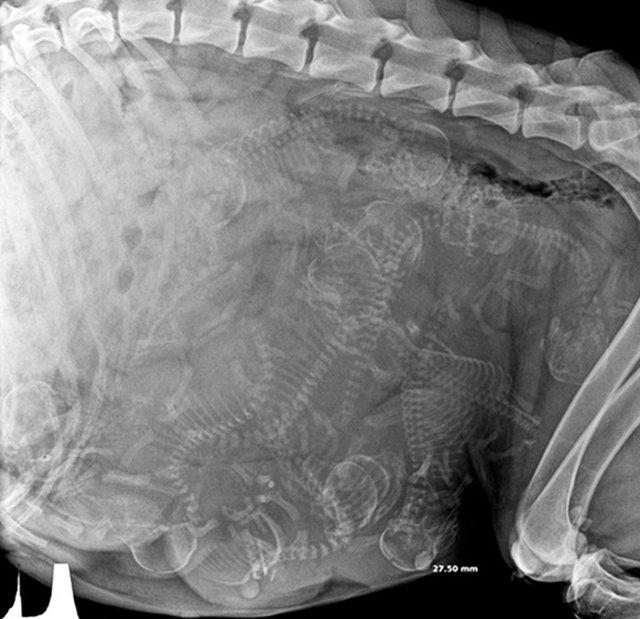

哈~這其實是動物懷孕的照片啦!美國《boredpanda》網站最近整理了一系列懷孕動物的X光照,從最常被人類飼養的貓、狗,乃至於蝙蝠、浣熊等都有,雖然小動物的誕生應該是可愛而溫馨,不過單看這些滿肚骨骸的X光照,還是覺得有點驚悚和詭異啊!

蛇